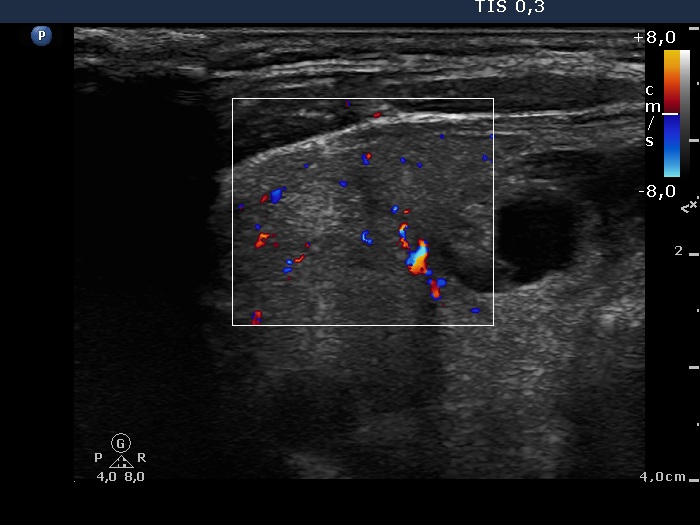

Right lobe, longitudinal scan

Right lobe, longitudinal view, color Doppler mode. The vascularization is not specific.